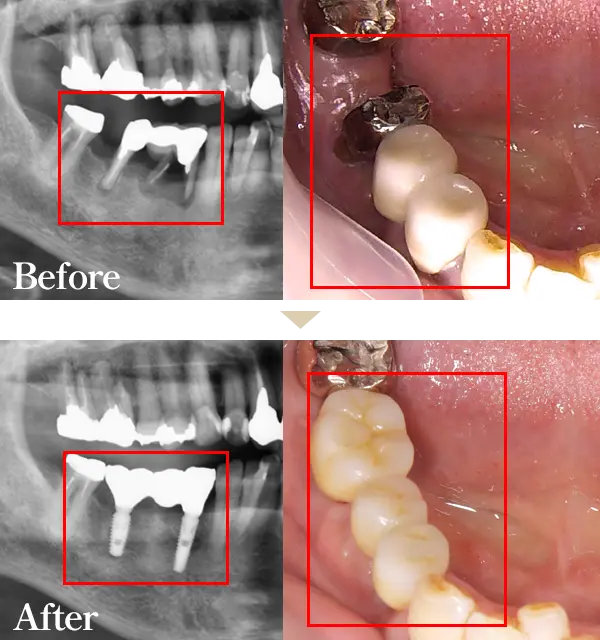

Wデンタルクリニックでは最短2か月で痛みの少ない先進のインプラント治療をご提供することができます。素材は強度にも優れ、身体にも優しい素材になっております。

まるで天然歯のような見た目、噛み応えなどがお勧めポイントです。健康な歯までも削らなくてはいけないブリッジ、違和感が強く噛む力も劣る入れ歯と比べてもメリットが多いのが特徴です。